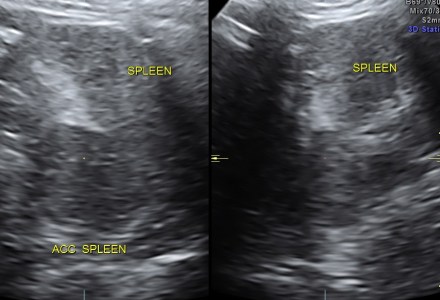

SPLENUNCULUS